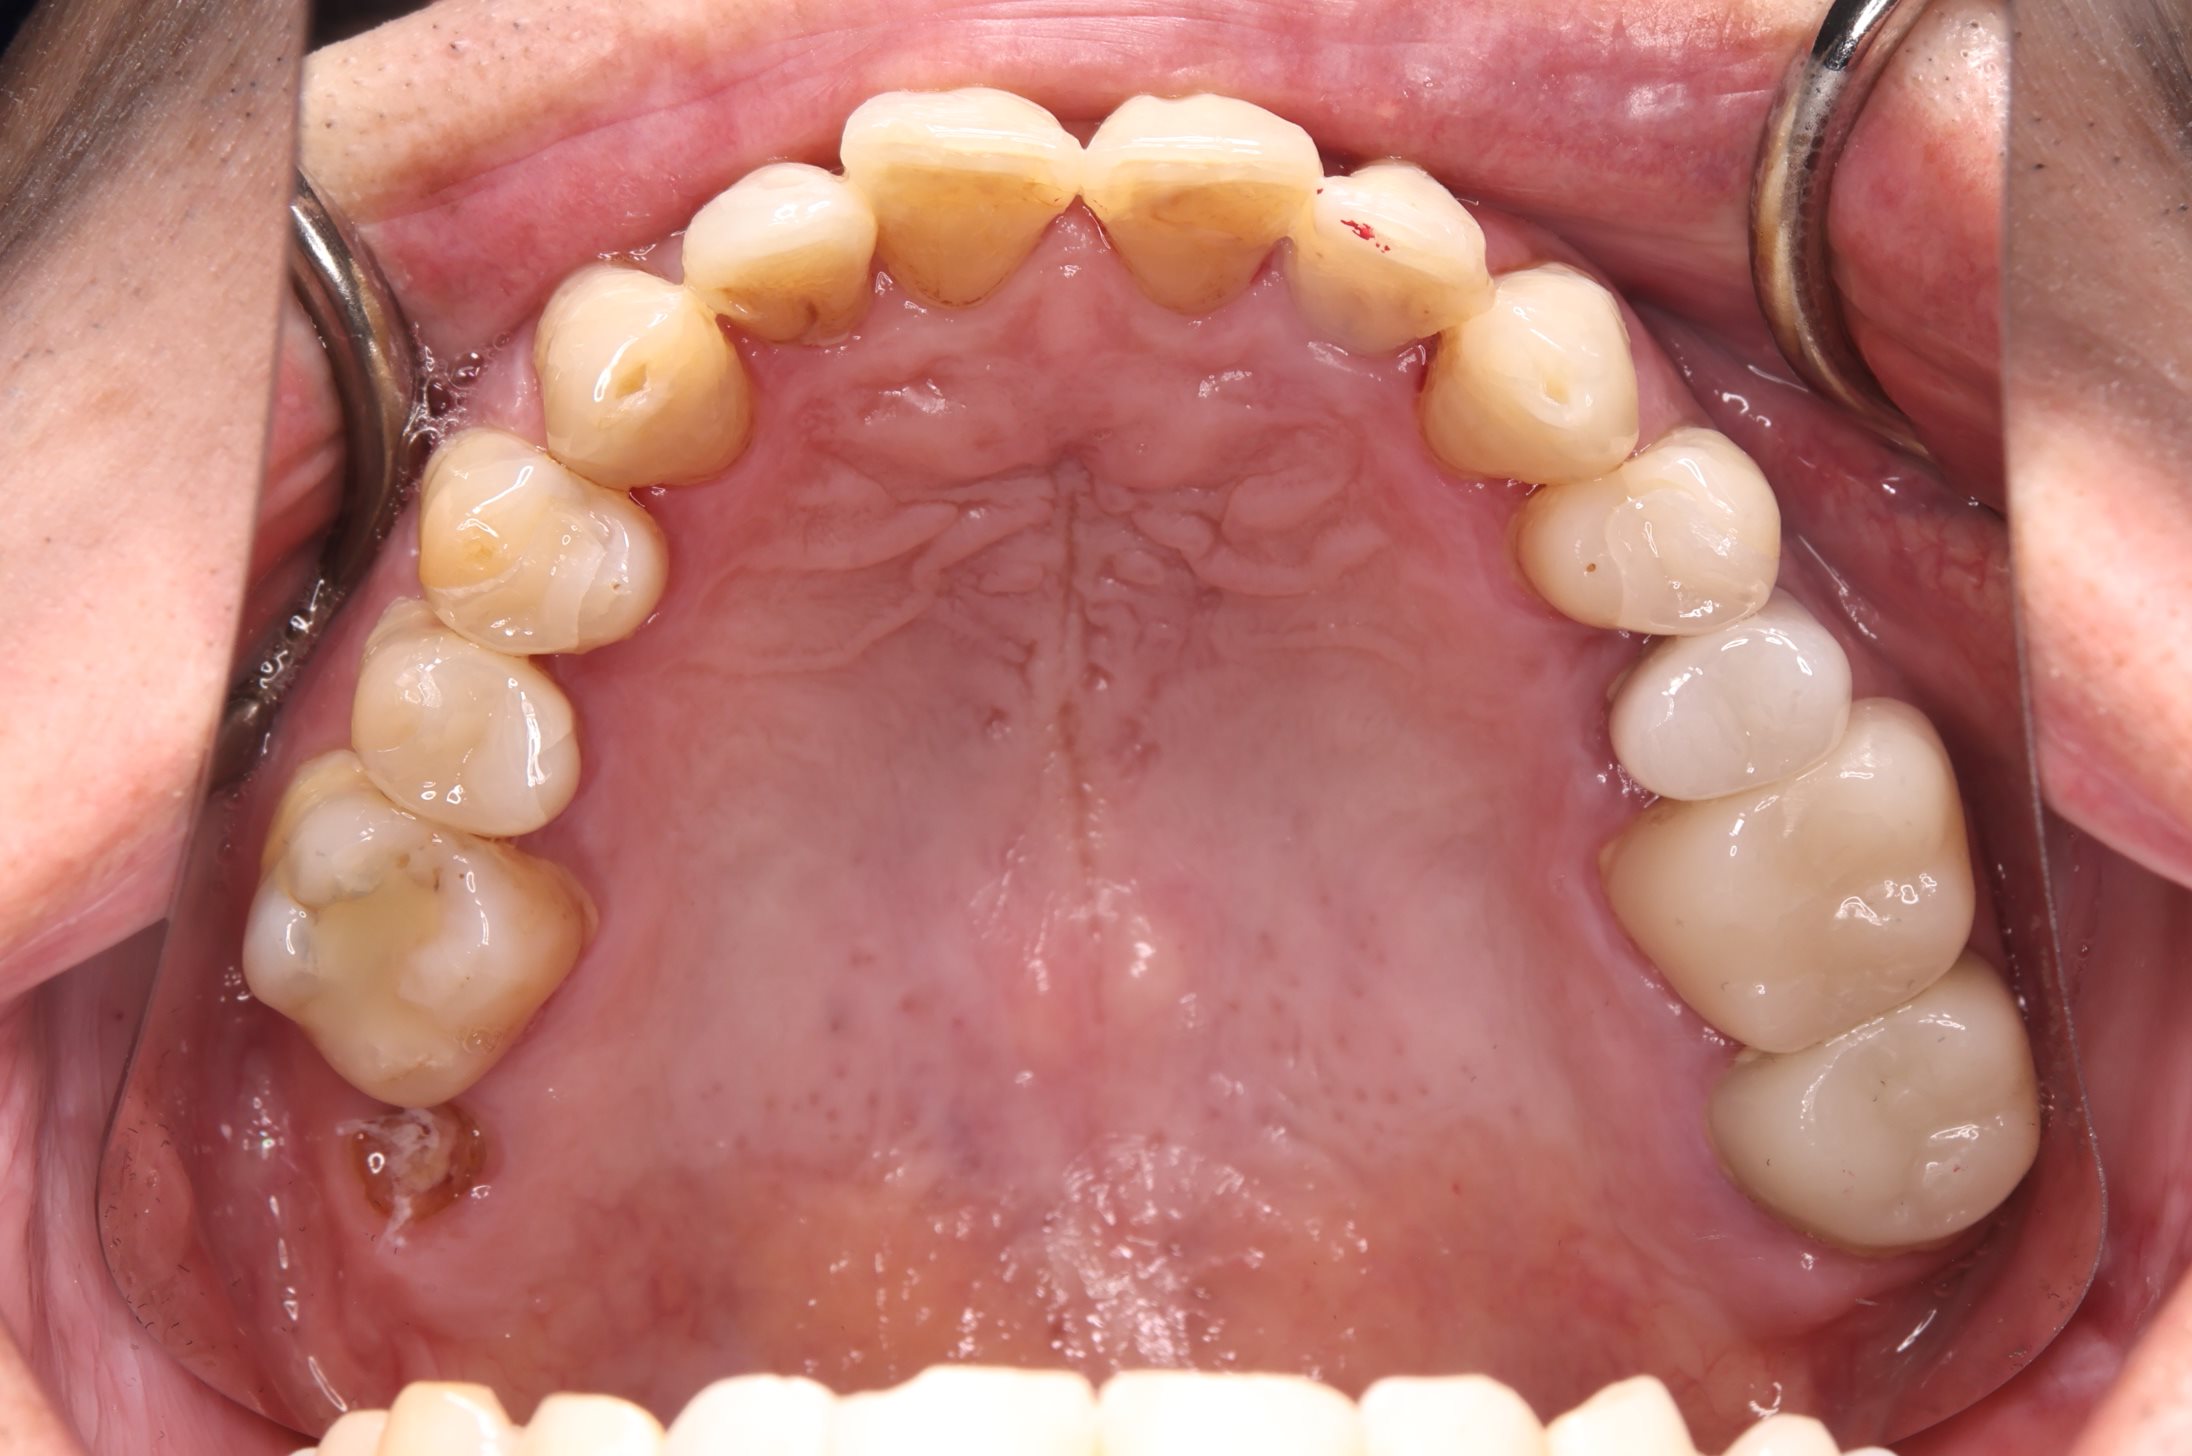

初診時の口腔内の状態:

お口全体に虫歯や歯周病の原因となるプラーク(歯垢)が多く付着していました。右上奥歯は重度の虫歯で歯冠部(歯の頭)が失われており、左下奥歯は過去の治療箇所から細菌が入り込み、根の先に炎症が起きている状態でした。

また、左右の奥歯にはWSD(楔状欠損)があり、知覚過敏も見られました。

Before